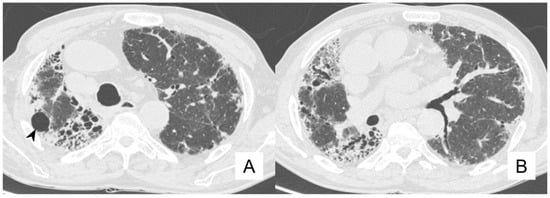

4.1. Lung Cancer